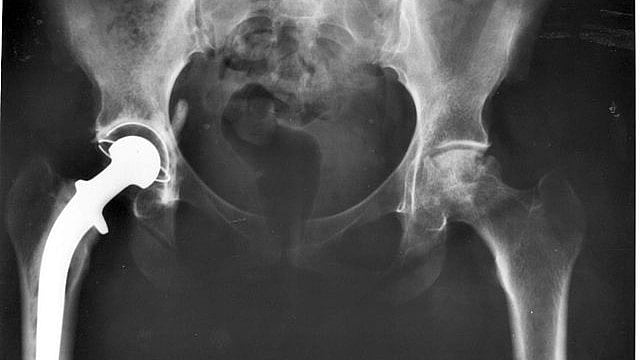

Postoperative AP hip radiograph after placement of antibiotic spacer

Postoperative AP hip radiograph after placement of antibiotic spacer Post Hip Replacement Antibiotics postoperative antibiotic prophylaxis is currently the standard of. learn about the causes, symptoms, and treatment of joint replacement infections, which may require antibiotics and surgery. the efficacy of prophylactic antibiotics for joint arthroplasty has been accepted for over 40 years dating back to the early. J am board fam med. authors of several studies reported good. Post Hip Replacement Antibiotics.